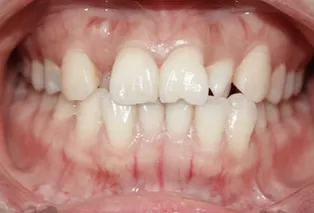

Femelle, âgée de 29 ans. Plainte principale: désalignement des dents, nécessitant une correction.

Encombrement et désalignement des dents maxillaires et mandibulaires, morsure croisée des dents 12 et 22 et désalignement de la ligne médiane.

Avant le traitement

Photos intra-orales